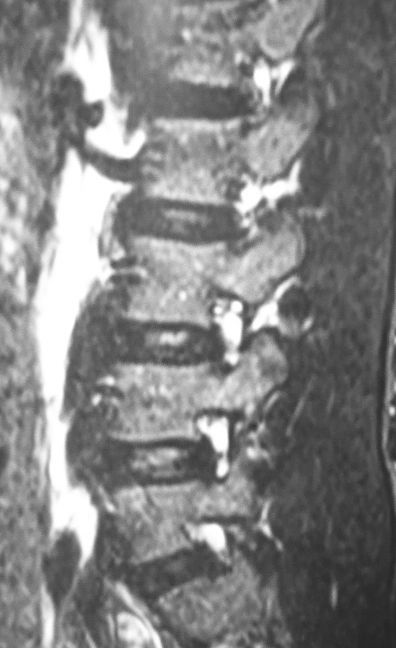

その後、ダーメンコルセットを作成して3ヶ月間常用とした上で、野球・スポーツ・体育の授業を完全に禁止しました。2ヵ月ぐらいしてから痛みが軽快し、本日腰椎MRIで最終確認を行いました。

11月のMRIでは高輝度だった左椎弓が、本日のMRIでは正常な輝度になっていることがはっきり分かります。めでたく、本日でダーメンコルセットを除去してスポーツ復帰を許可しました。

通常、単純X線像やCTで腰椎分離症の診断・治療を行うことが多いと思いますが、MRIの方が感度が高くて早期治療や治癒の判定には有効だと思います。

CTだと骨折の有無や骨癒合の判定がなかなか難しいことが多い印象です。分離症はそれほど数が多くないし患者さんも若いので、MRIを施行しても過剰医療に該当するとは思いません。

それに若年者に対するCTでの被爆量のことを考えると、あっさりとMRIで診断・治療を行う方が患者さんのためになるし、より合理的なのかなと思います。